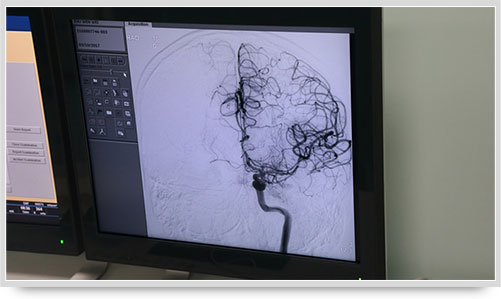

弓上造影、超選到頸內(nèi)動脈、椎動脈......在數(shù)字減影技術(shù)下,注入顯影劑后,導(dǎo)管經(jīng)患者右側(cè)股動脈在體內(nèi)推進(jìn),由于股動脈離腦血管距離較遠(yuǎn),中間“路程復(fù)雜”,對施術(shù)醫(yī)生的要求非常之高。

同時,手術(shù)臺前的液晶顯示儀屏幕上清晰地現(xiàn)顯出導(dǎo)管的路徑,在李主任的操作下準(zhǔn)確到達(dá)指定檢查部位,各條血管的“廬山真面目”清晰可見。